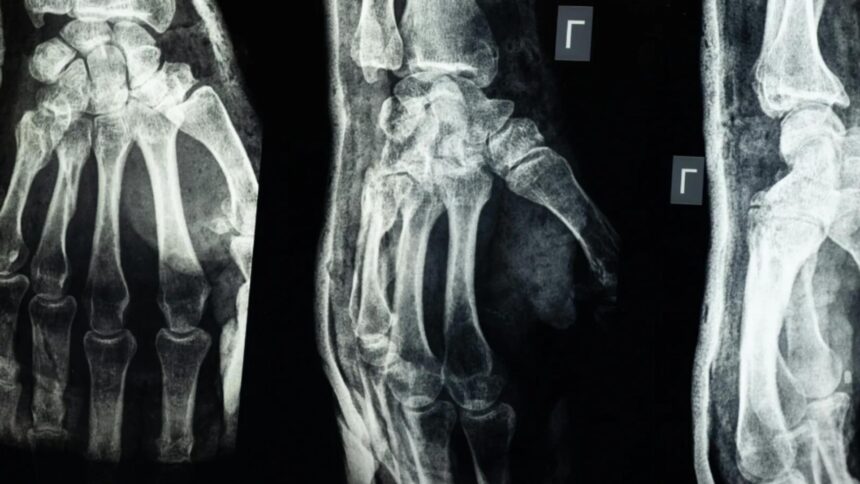

O echipă de cercetători din provincia Zhejiang, China, a dezvoltat un adeziv medical numit „Bone-02”, care poate repara fracturile osoase în doar 2-3 minute. Această soluție are potențialul de a înlocui implanturile metalice utilizate în prezent și de a reduce semnificativ timpul de recuperare al pacienților.

Testele de laborator și studiile clinice realizate pe peste 150 de pacienți au arătat că „Bone-02” oferă o rezistență comparabilă cu cea a implanturilor metalice. Forța de lipire a adezivului depășește 400 de livre, iar rezistența la compresiune atinge aproximativ 10 MPa.